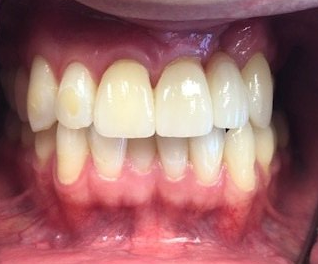

Resin Bonded Restorations (Composites)

This case illustrate a minor touch up with resin bonding. This is an alternative option when the patient does not want extensive treatment. One visit and no

anesthetic!